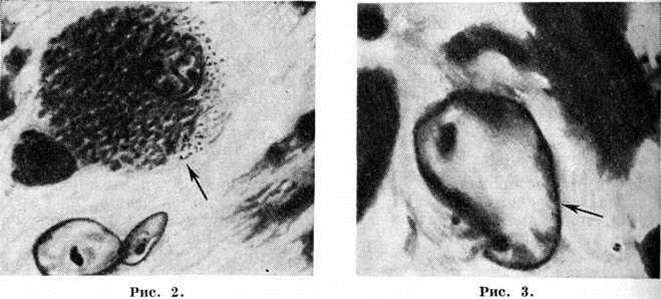

Печень вследствие атрофического цирроза уменьшена и бугриста (рисунок 4); участки нормальной ткани чередуются с участками некротическими, дегенерирующими и с островками регенерации; обильное новообразование сосудов приводит к появлению анастомозов между ветвями воротной и нижней полой вены. ПатогенезОсновную роль в патогенезе гепато-церебральная дистрофия играют генетически обусловленные нарушения обмена белков и меди. Нарушение синтеза белков ведёт к гипераминоацидурии (смотри Аминоацидурия) и гипопротеинемии (смотри Протеинемия), страдает и обмен нуклеопротеидов. Особенно большое значение имеет уменьшение церулоплазмина — белка, содержащего медь и обладающего ферментативными свойствами оксидазы (смотри Кровь, биохимия). В результате медь оказывается лишь рыхло связанной с альбумином и аминокислотами крови, легко отщепляется от них, в большом количестве выделяется с мочой (гиперкупрурия) и откладывается в тканях, главным образом в печени, головном мозге (подкорковые узлы) и роговице. Избыток свободной меди угнетает активность окислительных и некоторых других ферментов, что приводит к гибели клеток. Поражение печени с распадом её ткани и снижением барьерной функции ведёт к аутоинтоксикации продуктами гепатолиза и чужеродными продуктами, поступающими из кишечника (в частности, содержащими аммиак). В результате образования гистаминоподобных и других веществ ангиотоксического действия наступают тяжёлые расстройства кровообращения, усиливающие имеющуюся тканевую гипоксию. Вследствие этого гибель ткани отмечается прежде всего в местах, где потребность в кислороде особенно велика, то есть в головном мозге, особенно в чечевичных ядрах и коре больших полушарий. Кроме того, образуются и цитотоксические вещества, действующие непосредственно на элементы нервной ткани. Клиническая картинаГепато-церебральная дистрофия начинается в детском или молодом возрасте и имеет хронический прогрессирующее течение. Во многих случаях появлению симптомов поражения нервной системы предшествуют висцеральные расстройства в виде нарушения деятельности печени и желудочно-кишечного расстройств (желтуха, боли в правом подреберье, диспептические явления). Порой развивается выраженный гепато-лиенальный синдром (смотри). Чем сильнее страдает печень, тем раньше начинается и быстрее течёт заболевание. Со стороны нервной системы на первый план выступают экстрапирамидные симптомы в виде мышечной ригидности, гиперкинезов (рисунок 5) и расстройств психики. Пирамидные симптомы могут быть, но чаще отсутствуют. Чувствительность обычно не расстроена. Типичным симптомом болезни является кольцо Кайзера — Флейшера — отложение по периферии роговой оболочки содержащего медь зеленовато-бурого пигмента (цветной рисунок 7); оно более выражено при поздних формах заболевания. Иногда отмечается желтовато-коричневая пигментация кожи туловища и лица. Часты геморрагические явления (кровоточивость дёсен, носовые кровотечения, положительная проба жгута), мраморность кожи, акроцианоз. Капилляроскопия (смотри) обнаруживает атонию капилляров и застойность кровотока. Отмечаются суставные боли, профузные поты, остеопороз, ломкость костей. Патология печени клинически выявляется примерно у 30% больных, а в ряде случаев она может быть обнаружена только функциональными пробами, например пробой с нагрузкой галактозой, пробой Квика, пробой Бергманна — Эйльботта, бромсульфофталеиновой пробой; количество билирубина в крови и уробилина в моче обычно увеличено; изменены осадочные реакции Таката — Ара и Грея, обычны лейкопения и тромбоцитопения, гипохромная анемия (смотри Бромсульфофталеиновая проба, Квика — Пытеля проба, Коагуляционные пробы, Печень, методы исследования).